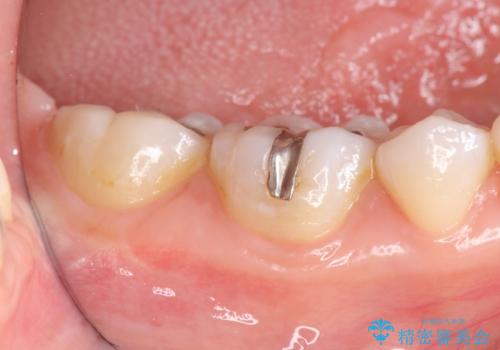

- 笑った時に見える銀歯を外したいと希望され来院されました。

銀歯の下には初期の虫歯も見られたので、除去後精密なシリコン印象を行いセラミックインレーを製作しました。